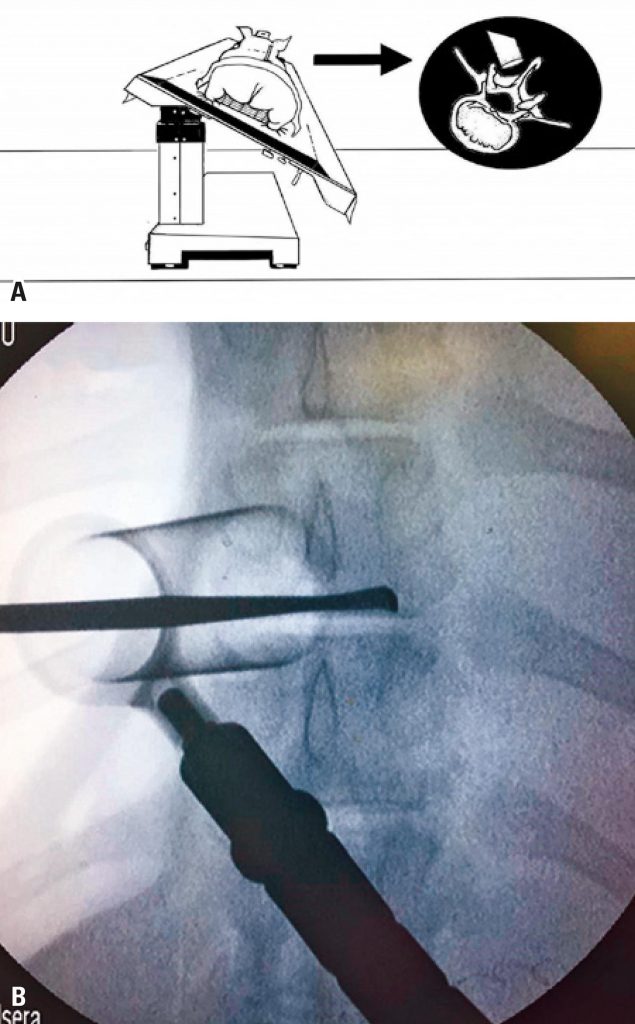

A total of 22 Large White class swine models, weighing between 60 and 80kg, were submitted to surgical simulations, performed during theoretical-practical courses for training surgical techniques (microsurgical and endoscopic lumbar decompression; percutaneous pedicular instrumentation; lateral access to the thoracic spine, and anterior and retroperitoneal to the lumbar spine, and management of complications) by 86 spine surgeons. For each surgical technique, porcine anatomy (similarities and differences in relation to human anatomy), access route, and dimensions of the instruments and implants used were evaluated. Thus, the authors describe the feasibility of each operative simulation, as well as suggestions to optimize training. Study results are descriptive, with figures and drawings.

Neural decompression surgeries (microsurgeries and endoscopic) and pedicular instrumentation presented higher similarities to surgery on humans. On the other hand, intradiscal procedures had limitations due to the narrow disc space in swines. We were able to simulate situations of surgical trauma in surgical complication scenarios, such as cerebrospinal fluid fistulas and excessive bleeding, with comparable realism to surgery on humans.